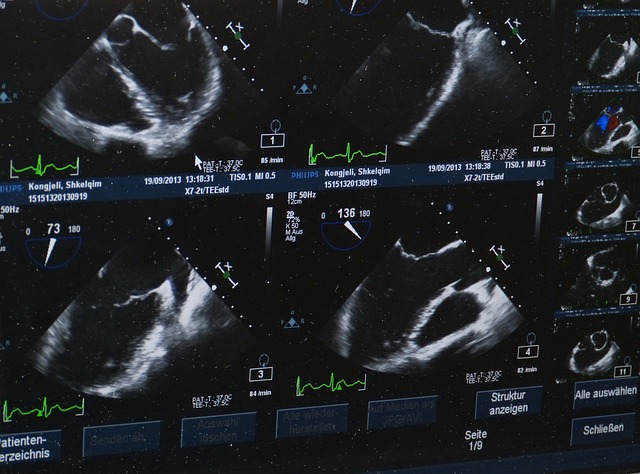

- 경동맥 초음파

목의 혈관 두께, 플라크 여부 확인 - 조기 진단에 매우 효과적